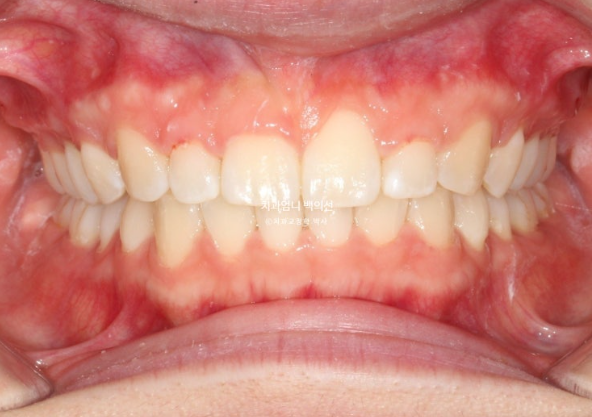

25.01

과개교합은 개선이 되었지만 잇몸 비대칭은 그대로입니다.

이 부분은 해결하기 위해 잇몸성형을 진행했습니다.

좋은 교합입니다.